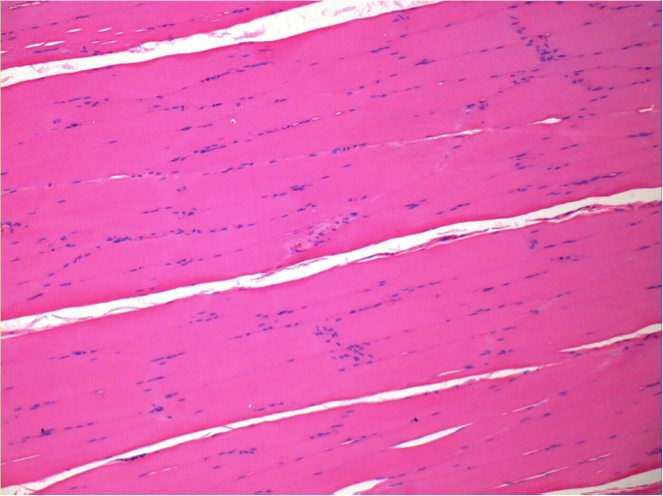

Controllo

Dopo iniezione di NaCl 0.5%

Commento : Niente da dichiarare dopo iniezione di soluzione fisiologica salina.

Sx:Pretibiale-Non trattato

Dx:Pretibiale-Dopo 0.1 ml NaCl 0.9% IM